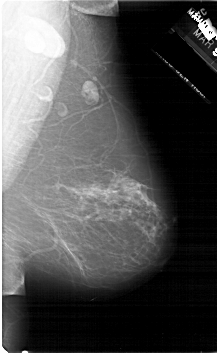

A_1300_1.LEFT_CC

LEFT_CC LINES 6856 PIXELS_PER_LINE 3826 BITS_PER_PIXEL 12 RESOLUTION 43.5 OVERLAY

FILE: A_1300_1.LEFT_CC.OVERLAY

TOTAL_ABNORMALITIES 1

ABNORMALITY 1

LESION_TYPE CALCIFICATION TYPE PUNCTATE-AMORPHOUS DISTRIBUTION CLUSTERED

ASSESSMENT 4

SUBTLETY 4

PATHOLOGY BENIGN

TOTAL_OUTLINES 1

BOUNDARY